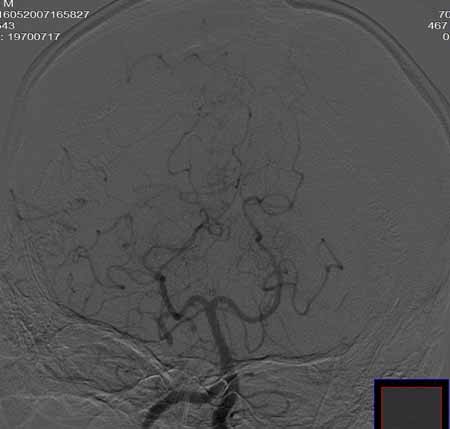

右侧颈总动脉闭塞(血栓形成),左侧大脑前动脉侧支、前交通动脉供应右侧大脑半球

右侧颈总动脉闭塞 ,左侧大脑前动脉侧支、前交通动脉供应右侧大脑半球,后交通部分开放 。缓慢代偿血流,分级3

右侧颈总动脉内见充盈缺损,提示血栓/栓子,原因:

1注意有无心房粘液瘤/血栓

2大动脉炎

抗凝治疗

右侧颈总a闭塞,右颈内颈外未显影,左侧未见异常,并通过wills环代偿右侧大脑半球血供